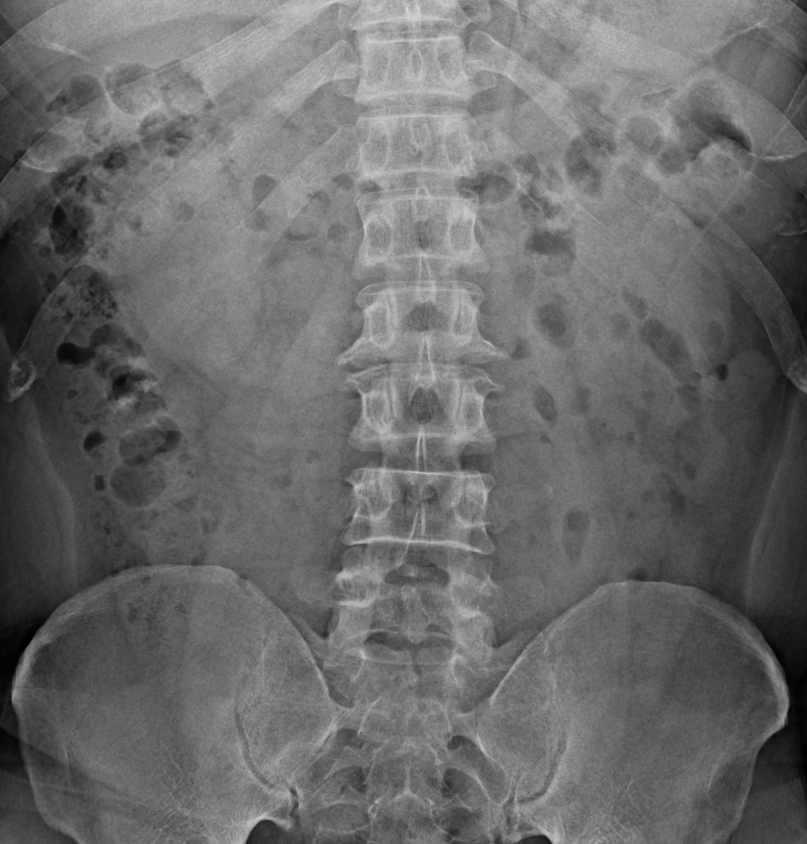

AP 촬영

- 중심선은 장골능(iliac crest) 위로 손가락 두개정도 높이.(L-3~4) 혹은 배꼽. (L-4~5 사이)

- 허리뼈 1번부터 5번까지 전체가 보여야 함.

- 위로 T11,12번(등뼈 11, 12번), 아래로는 Sacrum(천골)이 보여야 함

- 누운 자세로 촬영시 무릎을 세워 허리를 바닥에 더 붙인다. 이는 요추 전만을 줄여 추간관절이 더 잘 보일 수 있음.

강직성 척추염

- 허리뼈 및 주변 조직들이 딱딱하게 굳어 대나무같은 형상을 관찰 할 수 있다.

- AP사진의 경우 후방 요소들이 결합해 단검 모양을 관찰 할 수 있다.(dagger sign)

S1, 천추의 요추화

- 간혹 허리뼈가 5개가 아닌 6개로 관찰되는 환자들이 있다.

- 성장 과정에서 S1, 천추가 L6 6번허리뼈로 즉 요추화 하는 경우가 있는데, 일상 생활에는 큰 지장이 없다.